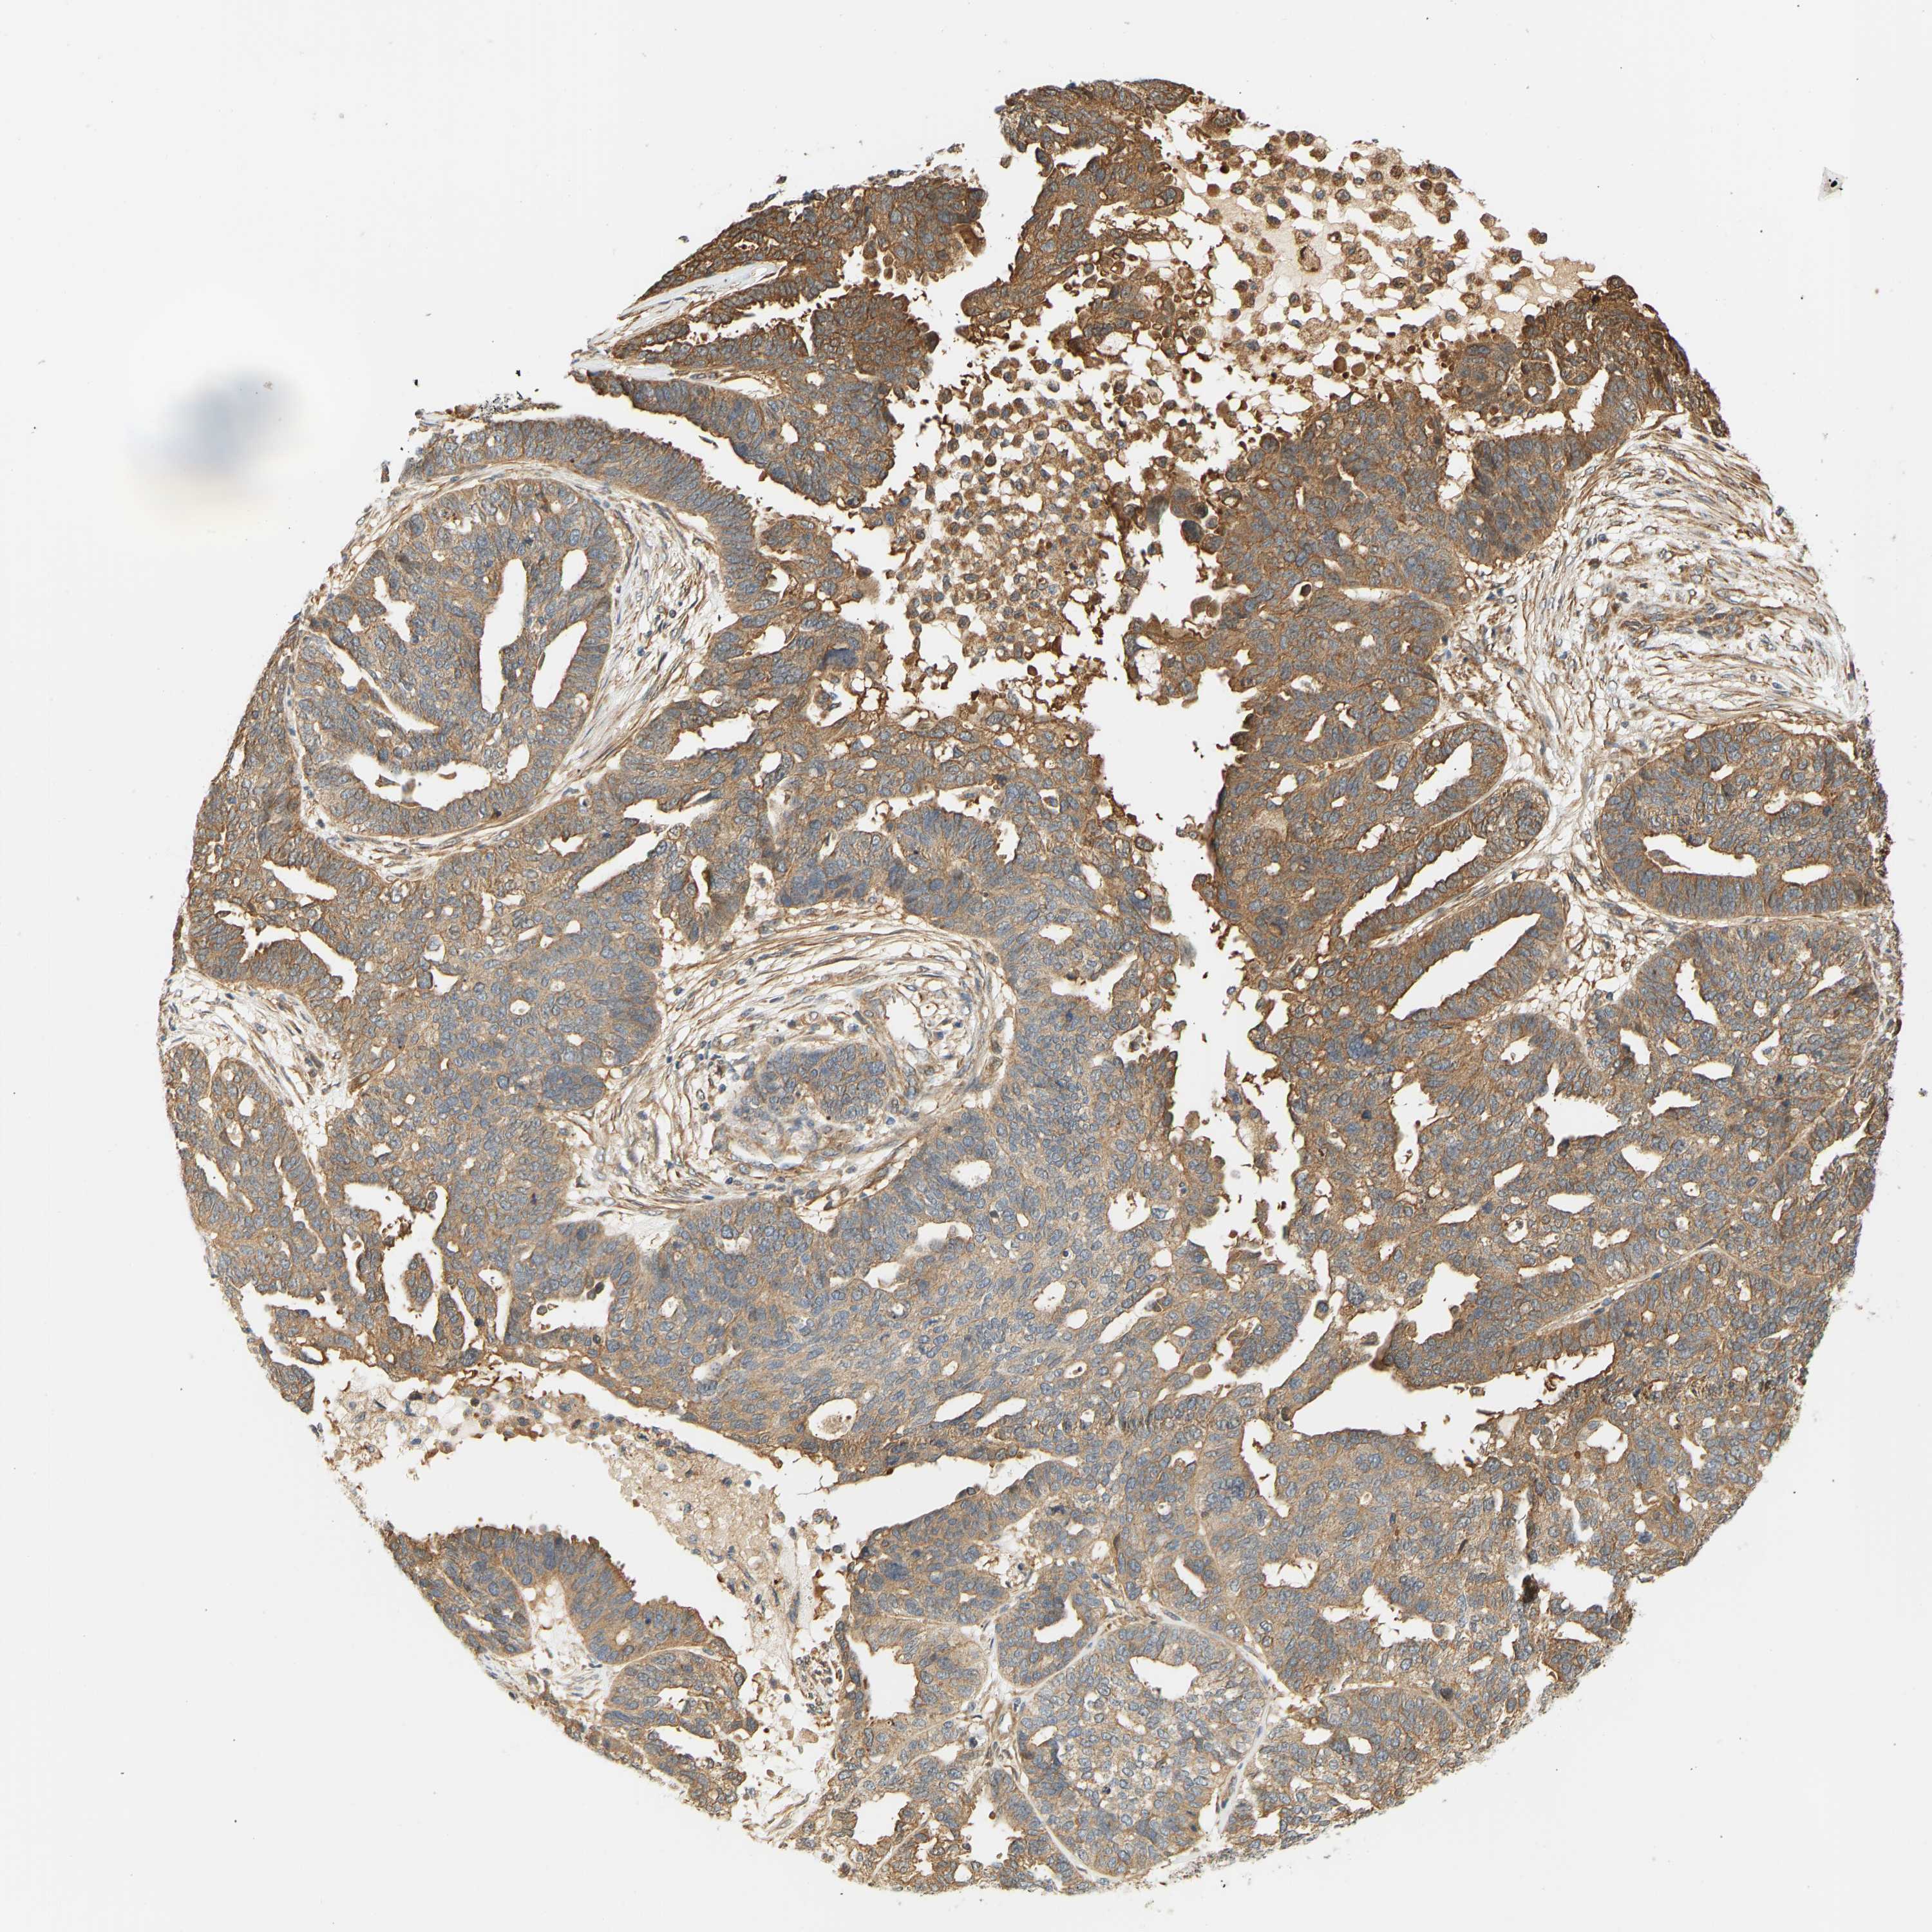

OVARIAN CANCER - Protein expressioni

A mouse-over function shows sample information and annotation data. Click on an image to view it in a full screen mode. Samples can be filtered based on level of antibody staining by selecting one or several of the following categories: high, medium, low and not detected. The assay and annotation is described here.

Note that samples used for immunohistochemistry by the Human Protein Atlas do not correspond to samples in the TCGA dataset.

Antibody stainingi

Antibody staining in the annotated cell types in the current human tissue is reported as not detected, low, medium, or high, based on conventional immunohistochemistry profiling in selected tissues. This score is based on the combination of the staining intensity and fraction of stained cells.

Each image is clickable and will lead to virtual microscopy that enables deeper exploration of all samples and also displays staining intensity scores, fraction scores and subcellular localization as well as patient and tissue information for each sample.

Antibody HPA018315

Staining

High

Medium

Low

Not detected

Intensity

Strong

Moderate

Weak

Negative

Quantity

>75%

75%-25%

<25%

None

Location

Nuclear

Cytoplasmic/membranous

Cytoplasmic/membranous,nuclear

Cystadenocarcinoma, serous, NOS

Carcinoma, endometroid

Cystadenocarcinoma, mucinous, NOS

Carcinoma, NOS